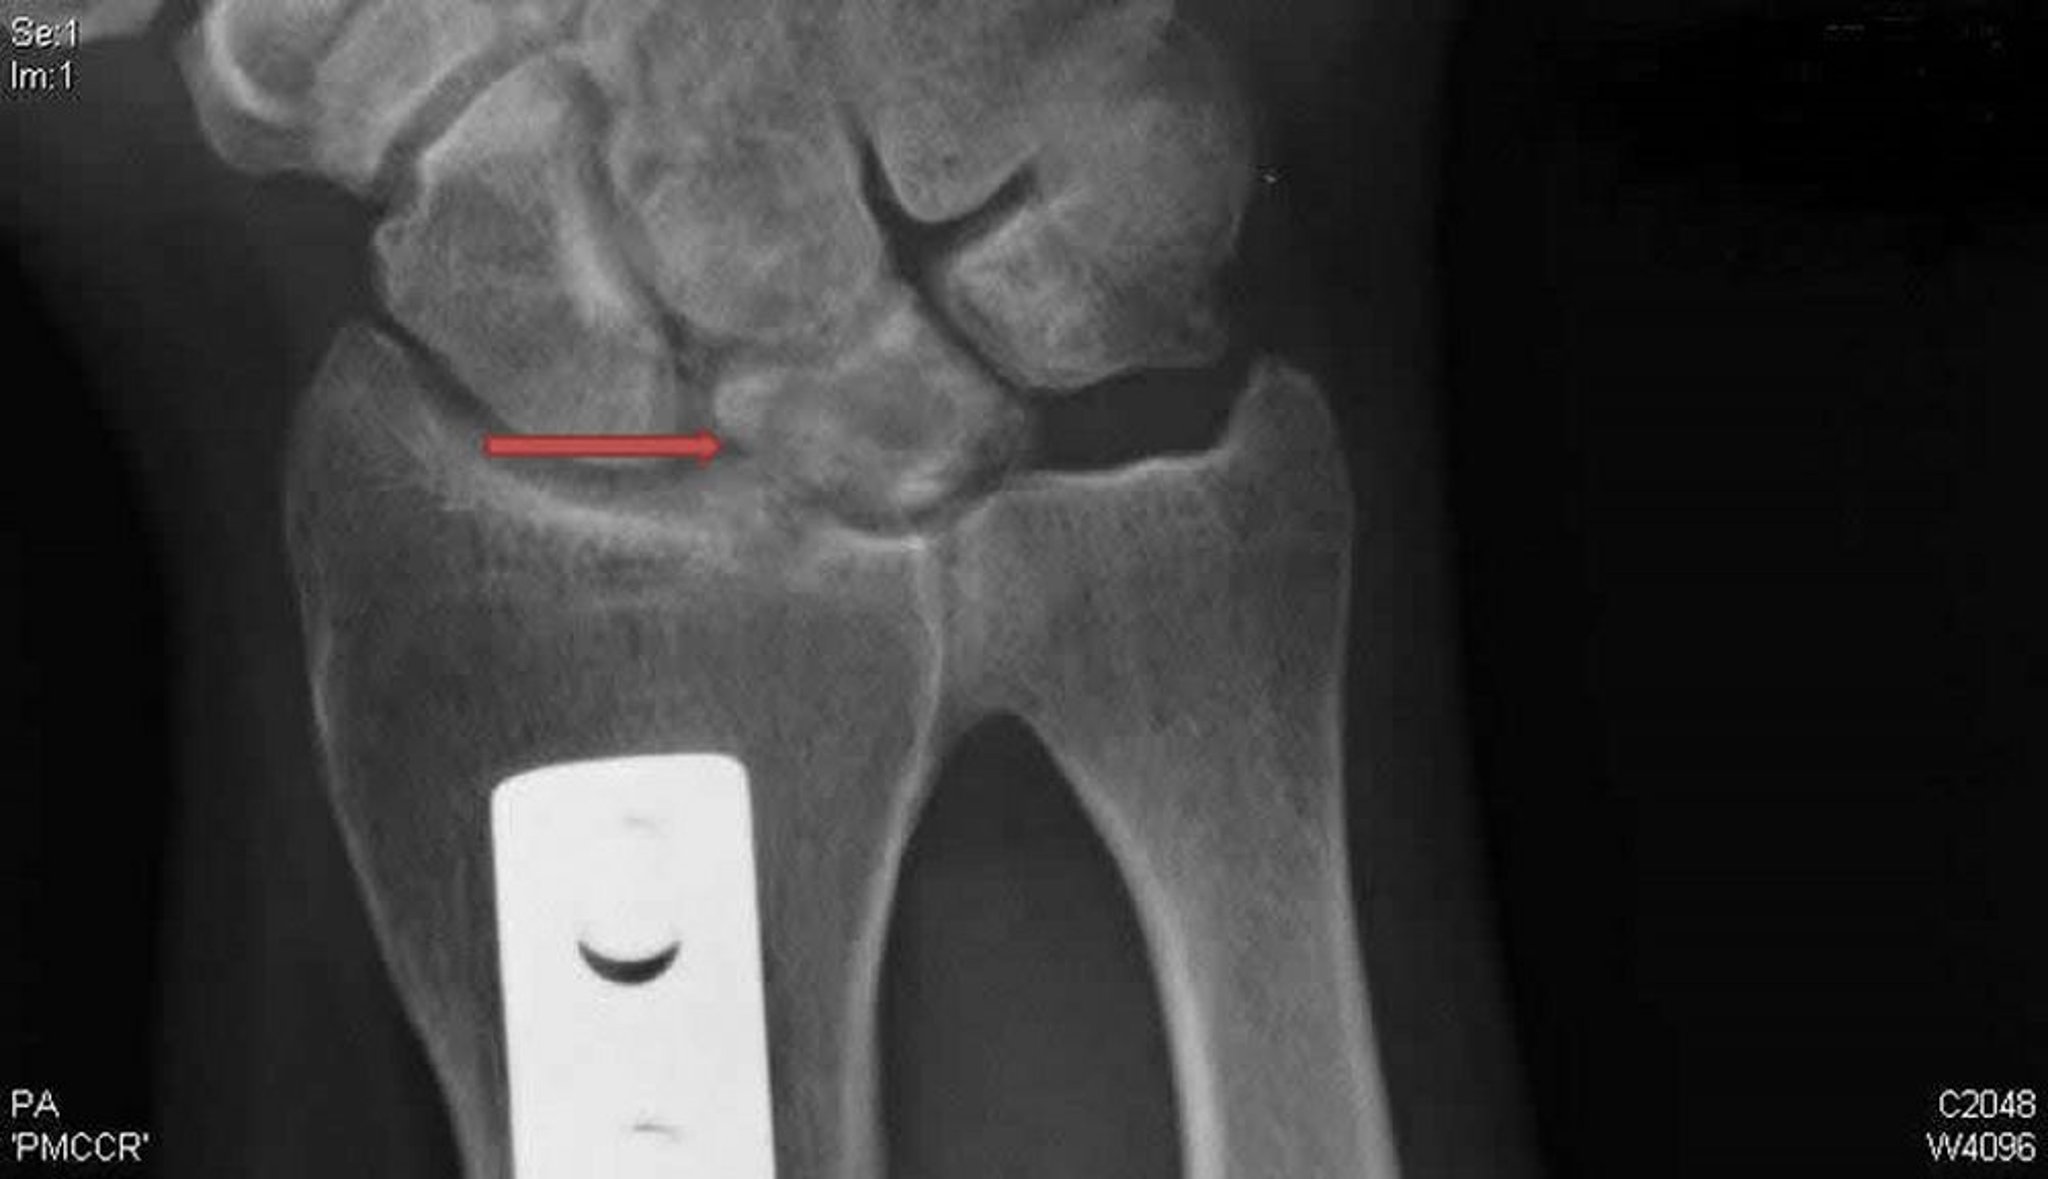

Maladie de Kienböck (radiographie de face)

Cette radiographie de face du poignet droit montre des kystes et une sclérose de l'os lunaire (flèche) typique de la maladie de Kienböck. La plaque de métal prouve une ostéotomie de raccourcissement radial effectuée pour décharger le semi-lunaire et potentiellement traiter cette maladie.

Rx courtoisie de David R. Steinberg, MD.